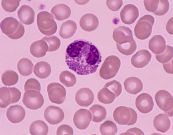

Tăng bạch cầu ái toan có thể là dấu hiệu cảnh báo về một số tình trạng sức khỏe như nhiễm ký sinh trùng, dị ứng hay thậm chí là ung thư. Để biết rõ hơn về bệnh lý này, mời các bạn tham khảo bài viết dưới đây.